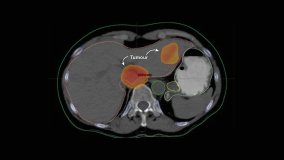

El comienzo de una nueva era: la radioterapia destruye más células cancerosas que nunca

La radiación revolucionó la medicina en 1901, cuando se utilizó por primera vez para tratar el cáncer. Sin embargo, su uso ha evolucionado únicamente hasta donde ha permitido la innovación técnica.